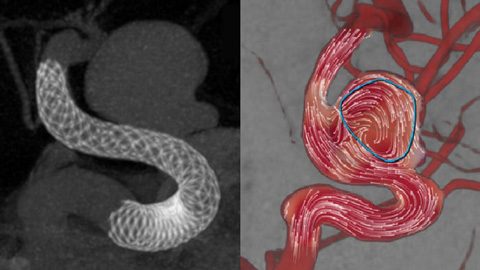

AneurysmFlow

Evaluar inmediatamente el impacto de los diversores de flujo

Poder evaluar de inmediato el impacto de los diversores de flujo es crucial durante el tratamiento. AneurysmFlow convierte la información de una adquisición de SmartCT Angio y las secuencias de flujo de la DSA 2D en valores de flujo cuantitativos.  Estos valores se utilizan para visualizar y cuantificar los patrones de flujo sanguíneo antes y después de la implantación del diversor de flujo en los aneurismas cerebrales.

Calcular el flujo sanguíneo después del tratamiento

Flujo en el aneurisma después del tratamiento

AneurysmFlow evalúa los cambios en el flujo sanguíneo en el aneurisma; para ello calcula el cambio en la amplitud media del flujo del aneurisma (relación MAFA [Mean Aneurysm Flow Amplitude]) antes y después de la colocación del diversor de flujo.